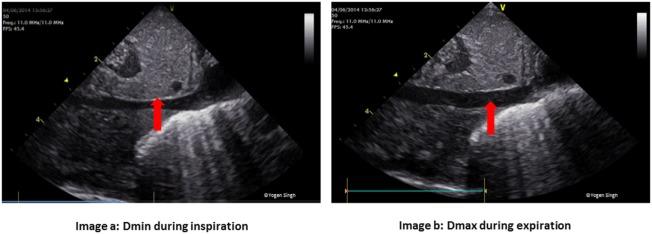

Shock in newborn infants has unique etiopathologic origins that require careful assessment to direct specific interventions. Early diagnosis is key to successful management. Unlike adults and pediatric patients, shock in newborn infants is often recognized in the uncompensated phase by the presence of hypotension, which may be too late. The routine methods of evaluation used in the adult and pediatric population are often invasive and less feasible. We aim to discuss the pathophysiology in shock in newborn infants, including the transitional changes at birth and unique features that contribute to the challenges in early identification. Special emphasis has been placed on bedside focused echocardiography/focused cardiac ultrasound, which can be used as an additional tool for early, neonatologist driven, ongoing evaluation and management. An approach to goal oriented management of shock has been described and how bed side functional echocardiography can help in making a logical choice of intervention (fluid therapy, inotropic therapy or vasopressor therapy) in infants with shock.

新生儿休克有独特的病因病理起源,需要仔细评估以指导具体干预措施。早期诊断是成功治疗的关键。与成人和儿科患者不同,新生儿休克常在失代偿期通过低血压被识别,而这可能为时已晚。成人和儿科常用的常规评估方法往往具有侵入性且不太可行。我们旨在讨论新生儿休克的病理生理学,包括出生时的过渡变化以及导致早期识别困难的独特特征。特别强调了床旁聚焦超声心动图/聚焦心脏超声,它可作为新生儿科医生主导的早期持续评估和管理的辅助工具。本文描述了一种针对休克的目标导向管理方法,以及床旁功能超声心动图如何有助于为休克婴儿合理选择干预措施(液体疗法、强心疗法或血管升压药疗法)。